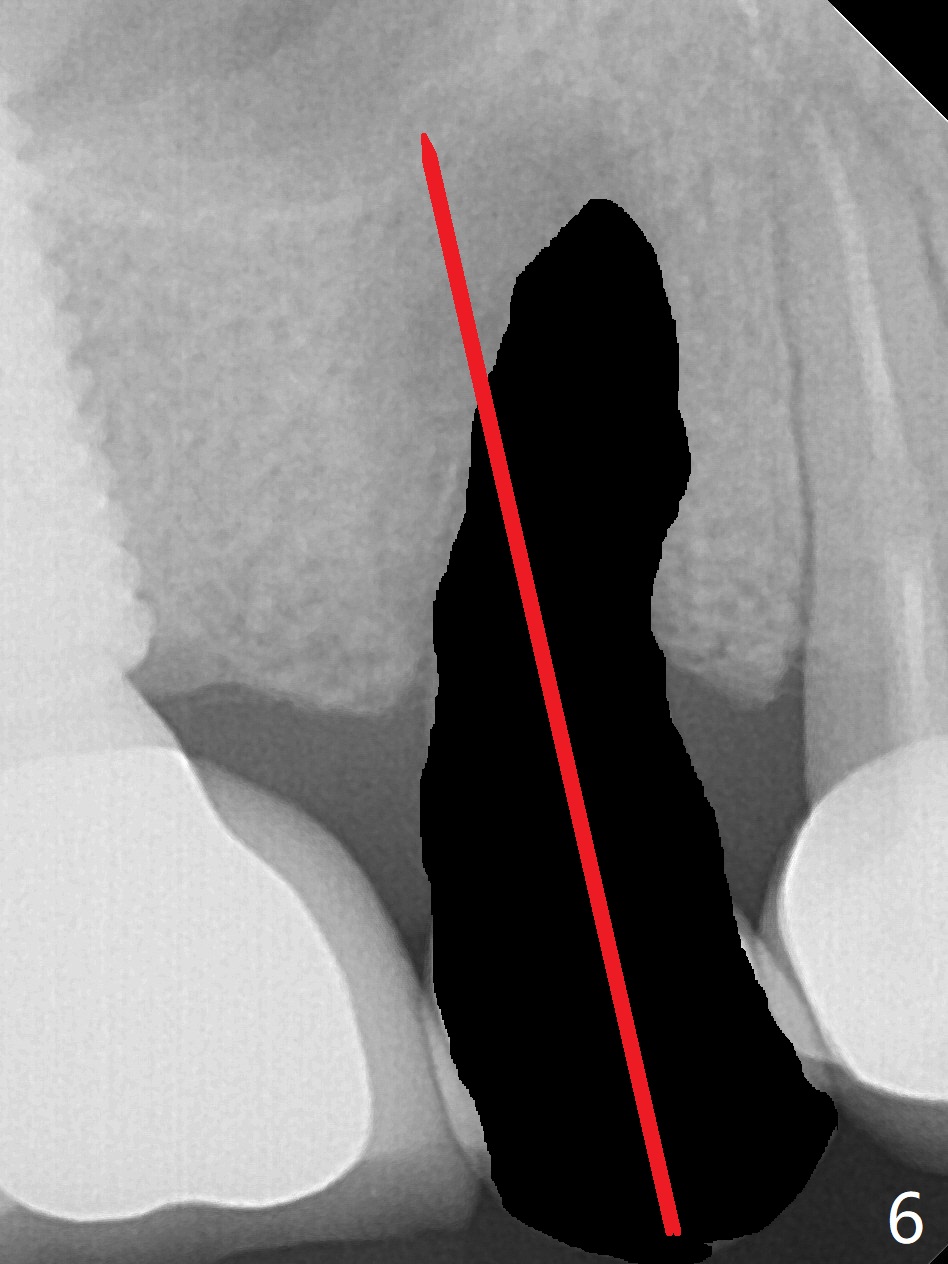

Crown/Implant Ratio

A 53-year-old man has signs of bruxism (Fig.1 diastema *) and root fracture or RCT failure at #4 (Fig.4 (large PARL *)). The RCT failure is related to overload of the affected tooth, which is in turn partially due to infraocclusion of the neighboring implant crown (Fig.1 arrows (implant positioning not ideal)) and partially to due to partial edentulism (Fig.2 missing teeth #14 and 18). For long term, limited ortho will be performed to upright and distalize the tooth #15 (Fig.3 arrow), followed by implants at #14 and 18. For now, the tooth #4 will be extracted (Fig.5), followed by osteotomy in the distal slope of the socket with guide (Fig.6 to get good trajectory). To place a bone-level implant (Fig.7 green), an abutment (blue) with long cuff (pink) is to be used. With poor implant/crown (white) ratio, stress occurs at the junction of the implant/abutment (red arrow), resulting in easy abutment screw loosening. In contrast, stress may be applied to directly to a tissue-level implant (Fig.8 arrow) with less likelihood of abutment screw loosening. The implant/crown ratio improves by approximately 5.5 mm. The roots of the teeth #15 and 16 are so close to each other that interference may occur when the tooth #15 is being uprighted (Fig.9). The empty socket of the tooth #4 is wide buccopalatal (Fig.10); the buccal plate is resorbed coronally (Fig.10 <) so that a 4.5 or 5 mm diameter implant should be placed palatal (Fig.11). Use sticky bone to repair the buccal plate defect and PRF membrane or plug for sinus lift. Following #15 uprighting and distalization, a 5x10 mm implant will be placed at #14; the ridge is triangular (Fig.12 <) so that bone trimmer is needed. A 10 mm long implant will be placed at #18 (Fig.14) to avoid perforating to the submandibular fossa (Fig.13 *).